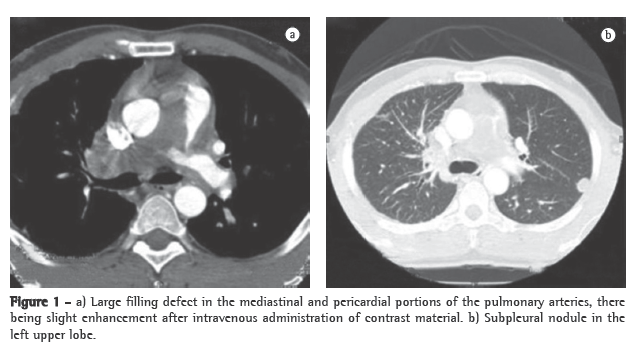

A transthoracic Doppler echocardiogram, which had been performed previously, showed moderate right heart enlargement, and pulmonary artery systolic pressure (PASP) was estimated to be 76 mmHg. A transesophageal echocardiogram demonstrated extensive thrombosis in the pulmonary artery trunk and PASP of 57 mmHg. Ultrasonography of the lower limbs revealed no signs of deep venous thrombosis. Lung perfusion scintigraphy, which was performed during hospitalization, showed low uptake in the view of the anterior and the apical-posterior segments of the left lung. The right lung was not visualized. Angiotomography of the chest revealed a large filling defect in the mediastinal and pericardial portion of the pulmonary trunk and arteries, there being enhancement of that defect after intravenous administration of contrast material (Figure 1a). In addition, there were predominantly peripheral nodules on the left (Figure 1b), as well as thickening of interlobular and peribronchovascular septa on the right, associated with upper lobe consolidation, moderate pericardial effusion and a mosaic attenuation pattern (Figure 2).

The clinical profile, together with the age of the patient, the failure of anticoagulant treatment, the tomographic alterations and the contrast enhancement, led to the hypothesis of intimal sarcoma-angiosarcoma-with pulmonary metastases. A CT-guided transthoracic biopsy of the left lung nodule was required. The specimen obtained consisted of a soft, reddish-tan filiform fragment, measuring 1.2 cm in length.

The case reported here draws attention to the need to raise the differential diagnosis in patients who are unresponsive to the current treatment of venous thromboembolism. Intimal sarcoma of the pulmonary artery is among the alternative diagnoses. Since iodinated contrast enhancement (angiotomography of the chest) can confirm the presence of the mass as well as its central location in the pulmonary trunk and arteries, which strongly suggest a diagnosis of intimal sarcoma of the pulmonary artery rather than that of CPTE, it constitutes a clue for making the former diagnosis. We emphasize the need for the proper use of the clinical methods currently available for the exact etiological definition of arterial pulmonary hypertension, prior to prescribing new medications (phosphodiesterase-5 inhibitors and inhibitors of endothelin receptors).(8,16)